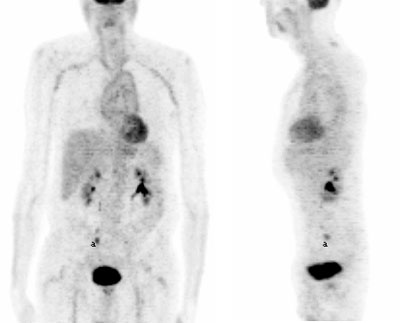

Fig. 20. - Imágenes coronal y lateral de tomografía por emisión de positrones de cuerpo completo. Varón de 19 años en estudio por linfoma. Se aprecia aumento fisiológico del metabolismo de la [18]FDG en músculos rectos anteriores, región cervical, supra e infraclavicular y paravertebral dorsal. En flexura de brazo izquierdo se observa el punto de inyección de la FDG por extravasación. En región testicular se identifica aumento fisiológico de la captación de la [18]FDG. volver